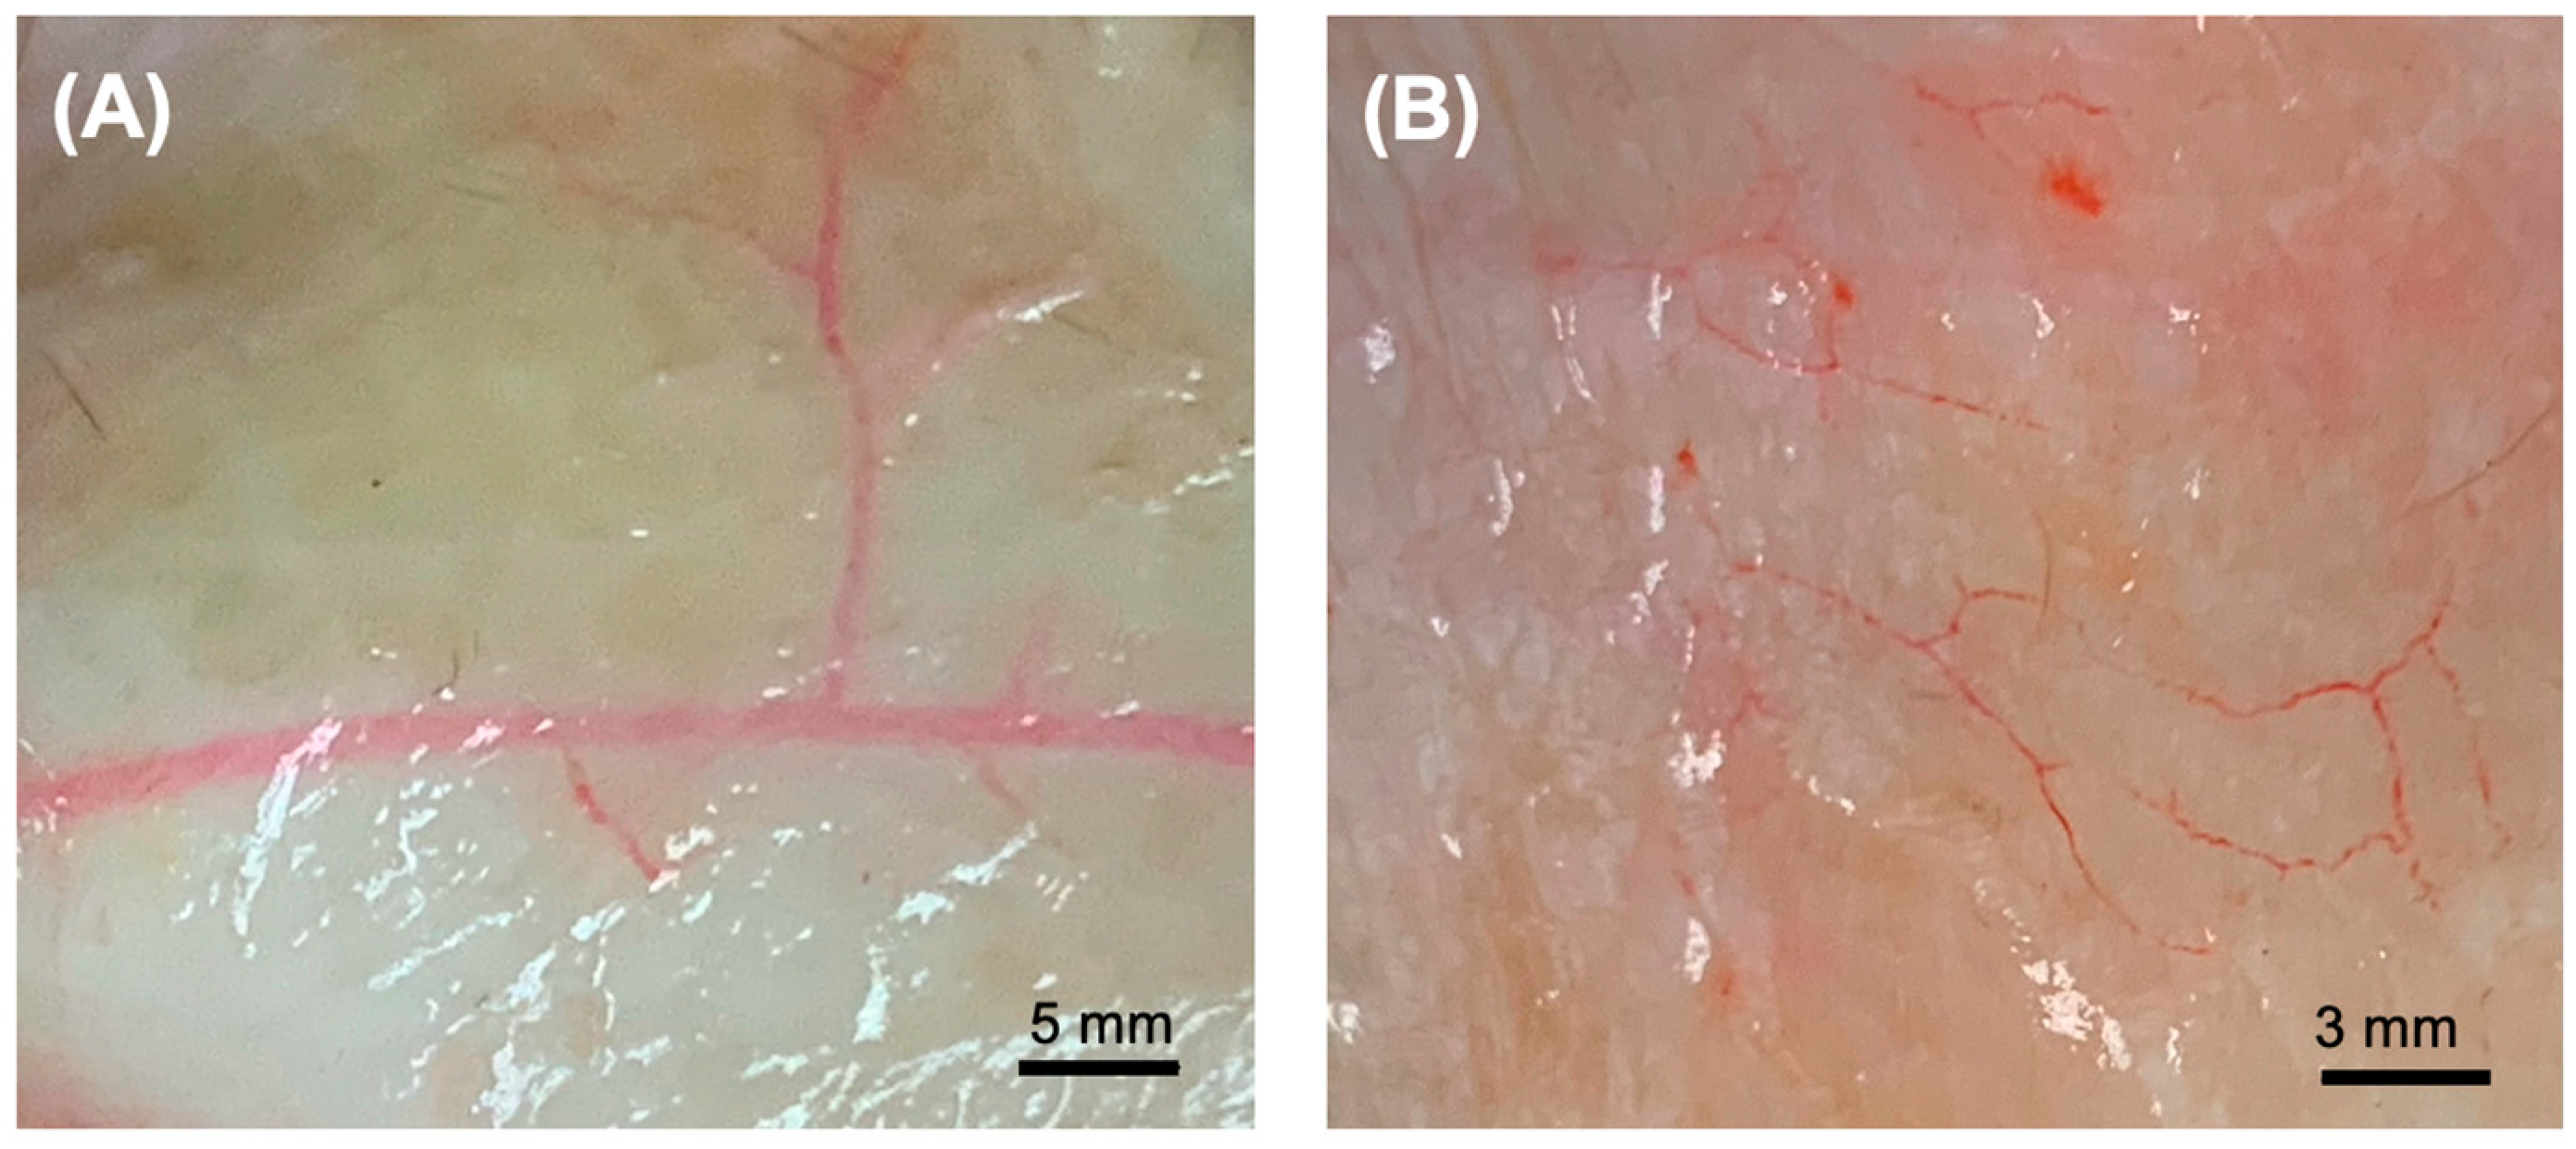

2.6. Assessment of Vascular Architecture

3.3. Microarchitectural and Mechanical Characteristics of Decellularized Facial Grafts